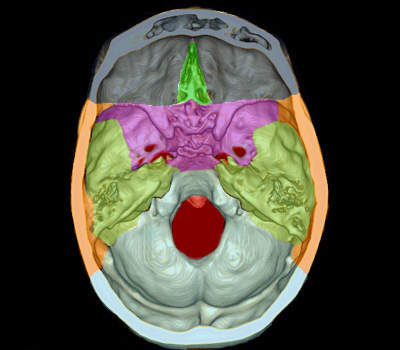

" À propos de l'écaille de l'os temporal on peut dire que :

A. Elle s'articule avec l'os occipital

B. Elle s'articule avec l'os sphénoïde

C. Elle s'articule avec l'os pariétal

D. Elle présente sur sa face interne les sillons de l'AMM

E. Elle limite en dedans la région temporale"